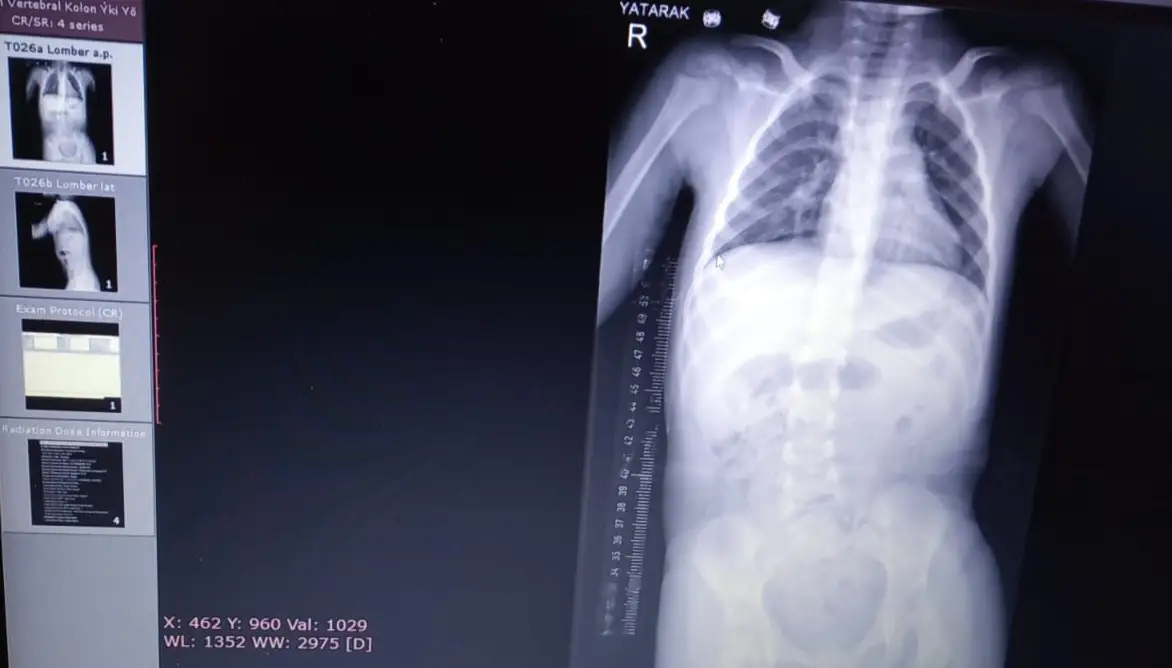

Но това не е всичко, малко след това се забеляза и изкривяване на гръбначния стълб на Мони и отново потърсих специалист в Турция, главно хирург горни крайници! Така стигнах до доц. Д-р Ахмет Аланай, който откри 21 градуса сколиоза която за сега не налага оперативна намеса!

На моя въпрос към професор А. Аланай дали Мони усеща болка в това състояние, ми бе обяснено, че това изкривяване причинява силен дискомфорт, болка във врата и кръста от натиска и състоянието й не е никак добро!

Но така или иначе предвид тежкия двигателен дефицит и състоянието на Мони, операция в бъдеще ще се наложи, която трае повече от 14 часа, поставят се пирони между прешлените и се води изключително тежка за нейната крехка възраст!

But that's not all, shortly after that Moni's spinal curvature was also noticed and again I sought a specialist in Turkey, mainly an upper limb surgeon! That's how I came to the doc. Dr. Ahmet Alanay, who found 21 degrees scoliosis which for now does not require surgical intervention!

To my question to prof. Alanay if Moni feels pain in this condition, I was explained that this curvature causes severe discomfort, pain in her neck and lower back from the pressure and her condition is not good at all!

But either way given Moni's severe mobility deficit and condition, surgery will be required in the future, which lasts over 14 hours, nails are inserted between the vertebrae and is extremely difficult for her tender age!